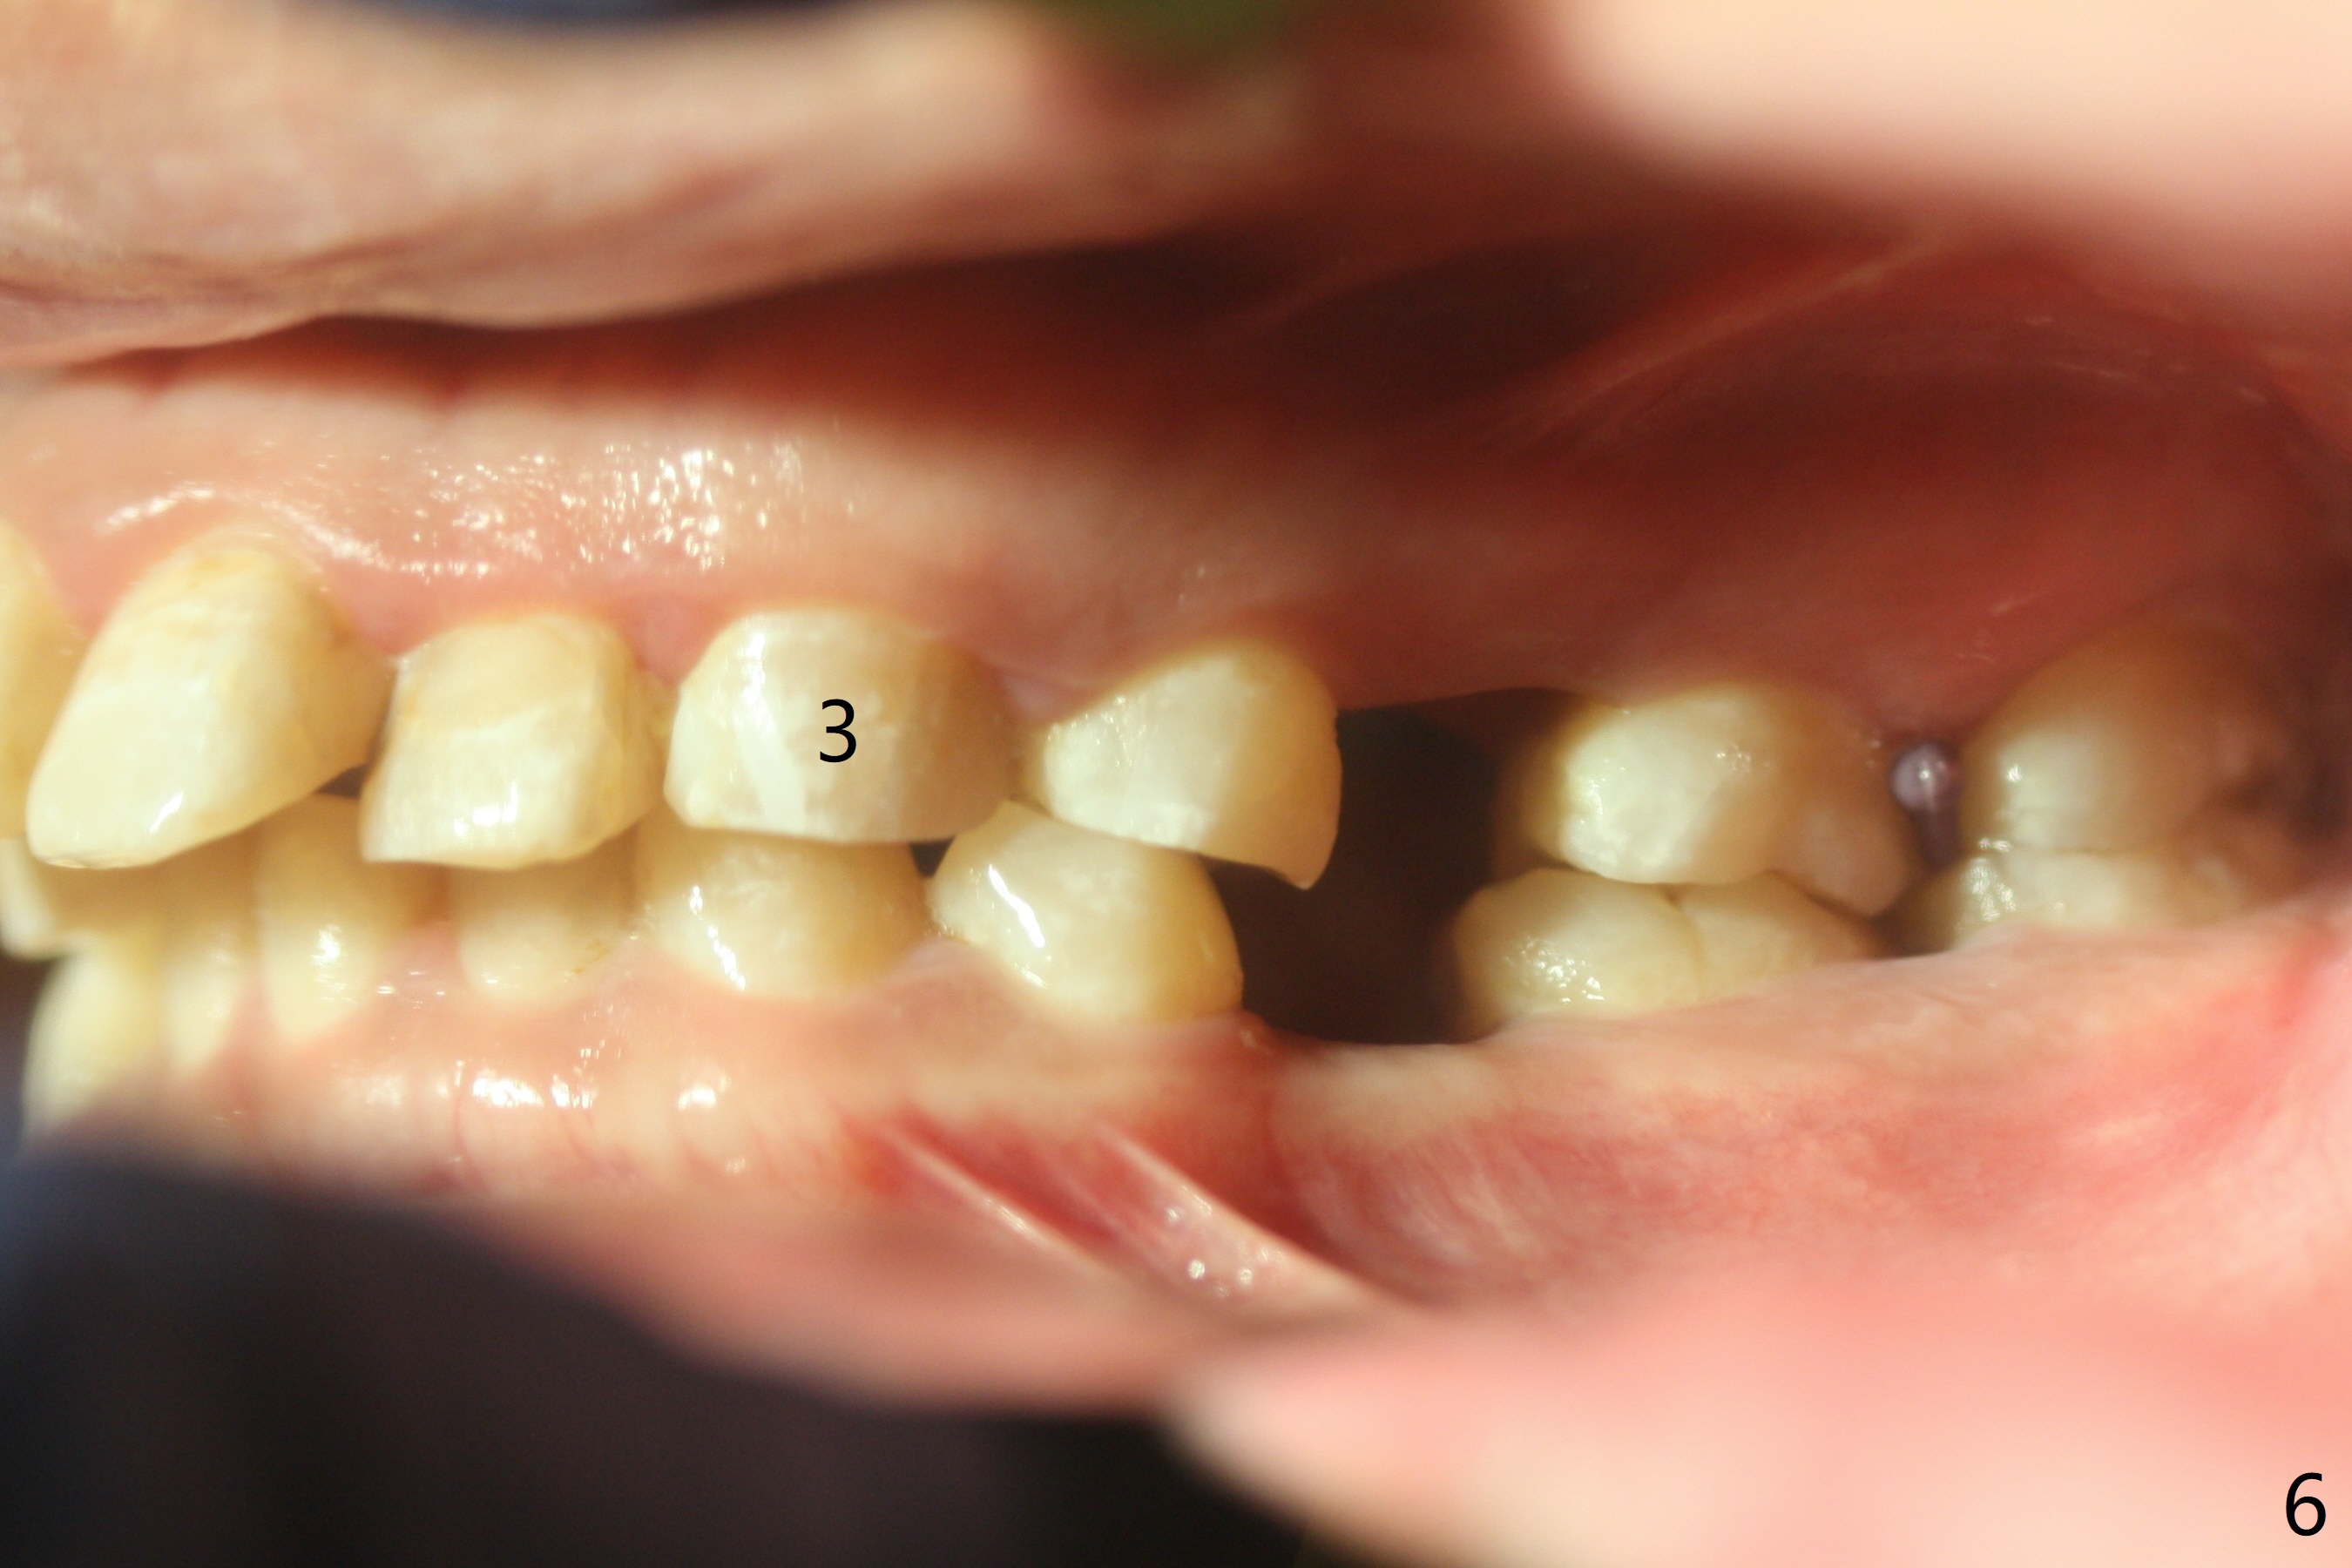

Severe crowding (Fig.1-7) appears to be alleviated especially 2 months after UR5 extraction. Diastemata seem to form mesial and distal to UR2 (Fig.8). Because of severe wear at UR3 (Fig.6), there is no bracket placement differential around it (Fig.8 (14 niti wire)). Lower bands and brackets are placed a week later (Fig.9-11). Because of tight space between LR4 and the opposing tooth (Fig.10), band adhesive is applied to L7 occlusal surface to open the bite (Fig.9). There is an abrupt kink of 12 niti wire between LL4 and 6 (Fig.11). The latter does not improve much in a month; the wires remain the same (Fig.12). For LL2, LR4 has been retracted for ~ 1 month (Fig.13). There is mild tension when 18 ss wire is inserted between LL4 and 6 five point five months post banding (Fig.14). UR4 has been distalized for a month using buccal power chains x3 resulting in rotation; to counter the rotation, a lingual button is placed with power chain x3 lingual and x2 buccal (Fig.15). With space gaining, it is time to finish definitive filling (Fig.16 *). Next visit check midlines, overjet, interdigitation, and molar classification. R4s distalize, but associate with rotation because of power chains buccal and lingual 8 months post banding (Fig.17,18). With the use of the same wires, power chains are applied lingual to continue distalization and rotation correction (Fig.20,21). Lingual buttons are placed at L2s buccalization (Fig.19) and mesialization (Fig.22,23). It appears that space should be created distal to LR3. That is that the lower anterior teeth should be shifted to the right, although it may be not appropriate for the midline.